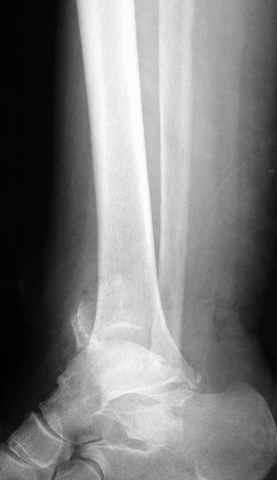

Pilon fracture:

ET> ЕЧ При подобных переломах фиксация малоберцовой кости обеспечивает

ET> низведение латерального тибиального фрагмента - появляется ориентир для

-Появляется ориентир и остов, на чем можно строить восстановление, почему сперва малоберцовую, впервые обьяснили и описали (Pylon type and Ankle fractures) в середине 50х Rienau и Gay.

Восстановливая длину и ротацию малоберцовой кости, затем относительно легче произвести реставрацию остальных элементов перелома дистального эпиметафиза болшеберцовой кости.

конец малоберцевой кости, к нему прикрепляется латеральный суставной фрагмент дистального эпиметафиза большеберцовой кости (как на снимке)

и таранная кость, которые при репозиции малоберцовой кости репонируются автоматически.